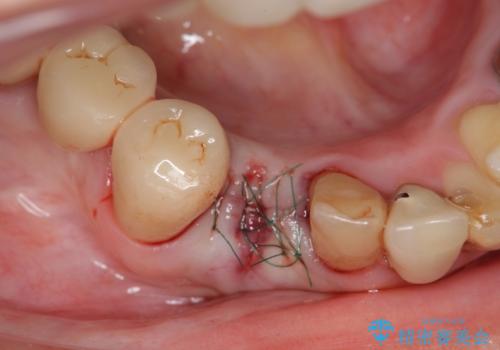

X線写真および歯周組織検査より、歯の破折 周囲骨の高度な吸収が認められました。

抜歯後、インプラントによる審美・機能改善を希望されたのでインプラント埋入に先立ち吸収した骨の再生を計画します。

歯を失う原因が虫歯や根尖病変などはなく、歯周病や歯の破折等周囲の骨を吸収する原因の場合はインプラント治療を行うに先立ち骨の造成が必要なことがあります。